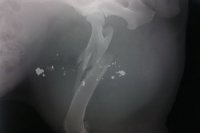

V Dražovciach došlo k streľbe: Živým terčom sa stal pes, FOTO